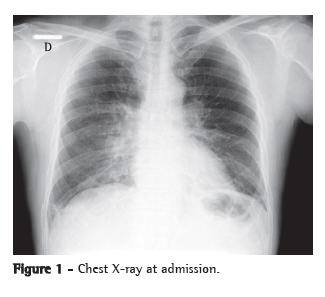

The patient was admitted to the ICU and treated with oseltamivir, ceftriaxone, azithromycin and a corticosteroid. He received ventilatory support with intermittent positive pressure breathing, which was maintained at 50% via a Venturi mask, at a resting SpO2 of 92%. The patient progressively improved and was discharged from the ICU ten days later, presenting an SpO2 of 94% on room air, together with radiological improvement (Figure 3). He developed no fever or hemodynamic instability during the hospital stay.